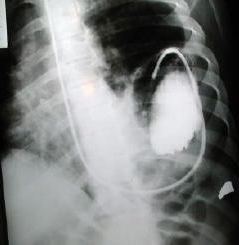

Sonda nasogastrica con contraste

Evidencia el fundus gastrico en la base del hemi tórax izquierdo, (contraste digestivo y la sonda llena de contenido radiopaco), unión cardioesofagica in situ, anillo o brecha diafragmática, borramiento del seno costo diafragmático  y borramiento de la linea diafragmática Izquierda, se confirma la presencia de hernia diafragmática Izquierda.